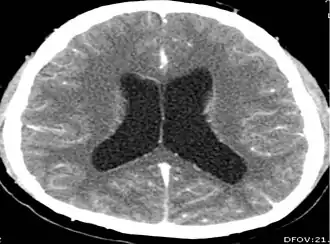

CT scan of neurocysticercosis and hydrocephalus

CT scan of the head of a patient with neurocysticercosis showing presence of hydrocephalus and dilation of ventricles[17]

Intracranial hypertension – a build-up of pressure around the brain – is associated with neurocysticercosis and may be accompanied by other symptoms.[5] More common in extraparenchymal neurocysticercosis,[9] it is most frequently caused by buildup of cerebrospinal fluid (CSF) in the brain.[5][16] Hydrocephalus can be related to granular ependymitis, compression of the CSF pathways by cysts, cysticercotic arachnoiditis, and inflammation or cysts blocking ventricles.[5][9] Large subarachnoid cysts and cyst clumps can also cause a mass effect and intracranial hypertension, with or without hydrocephalus.[18] Intracranial hypertension can present as episodic loss of consciousness when moving the head, known as Bruns syndrome; [5] it may be subacute or chronic.[16] Cysticercotic encephalitis, which is a severe type of neurocysticercosis usually affecting younger women and children, can also cause intracranial hypertension.[9] Cysticercotic encephalitis is characterized by seizures, intracranial hypertension, clouding of consciousness, optic disc swelling, headache, reduction of visual acuity, and vomiting.[19][20]